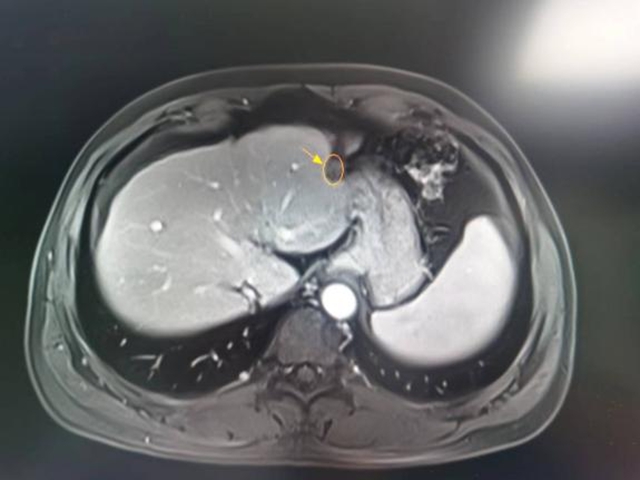

40多岁的解先生乙肝两对半异常有20余年了,2015年时在当地医院做CT检查提示:肝左外叶结节影,考虑为原发性肝癌。为寻求进一步诊治,解先生来到了西南医科大学附属中医医院就诊,肝胆病科医师接诊后为其完善了相关检查,确诊为原发性肝癌。

综合考量病情后,肝胆病科团队为解先生制定“肝动脉灌注化疗+超声引导下肝肿瘤消融”微创治疗方案。术前准备就绪后,肝胆病科团队顺利为其实施了手术,术后给予保肝降酶、抑酸护胃等处理,配合中医中药活血化瘀、疏肝解郁。而后定期随访复查,至今未发现肿瘤复发。

术前

术后